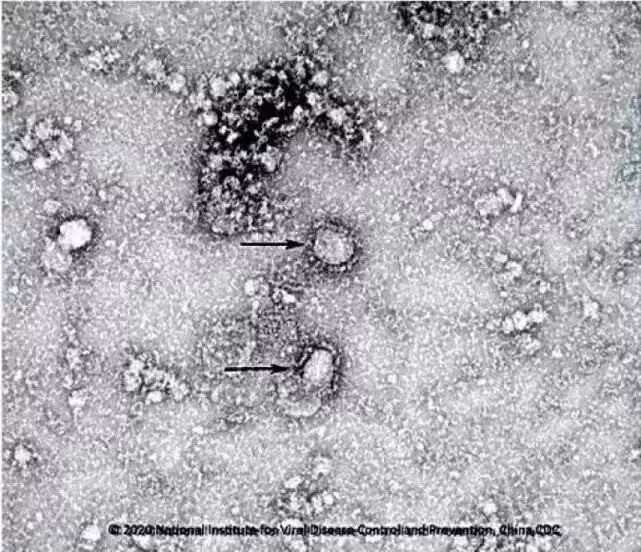

中国疾控中心病毒所所长许文波,26日表示目前该中心开始启动新型冠状病毒的疫苗研发,目前已经成功分离病毒

正在筛选种子毒株,此外,中国疾控中心正在进行新型冠状病毒肺炎的药物筛选。

中国疾控中心已成功分离我国首株新型冠状病毒毒种,官方治疗新型冠状病毒肺炎的中药方来了!